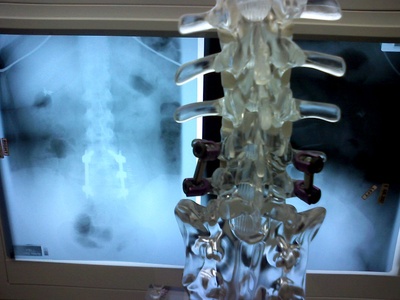

Spinal Fusion

Permanent joining of two or more vertebrae using bone grafts and hardware to stabilize the spine for pain or deformity.